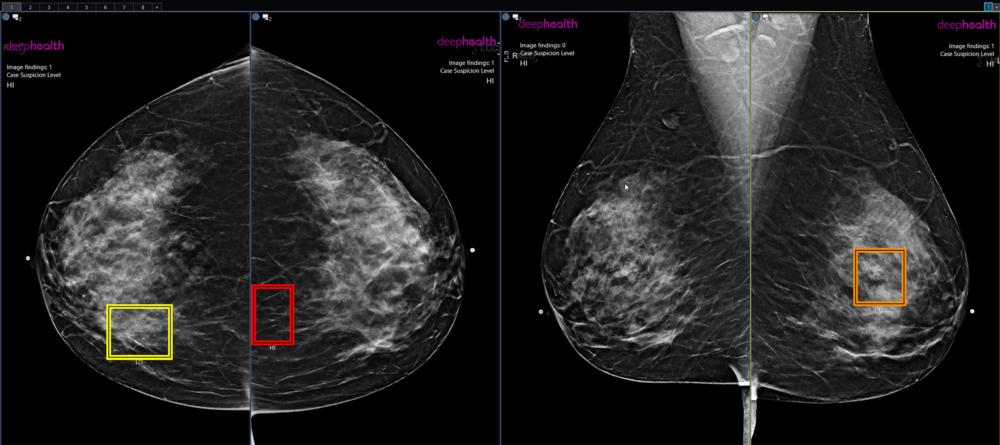

Figure 1. AI enhanced screening mammography.

Figure 2. Example of abnormal mammogram.